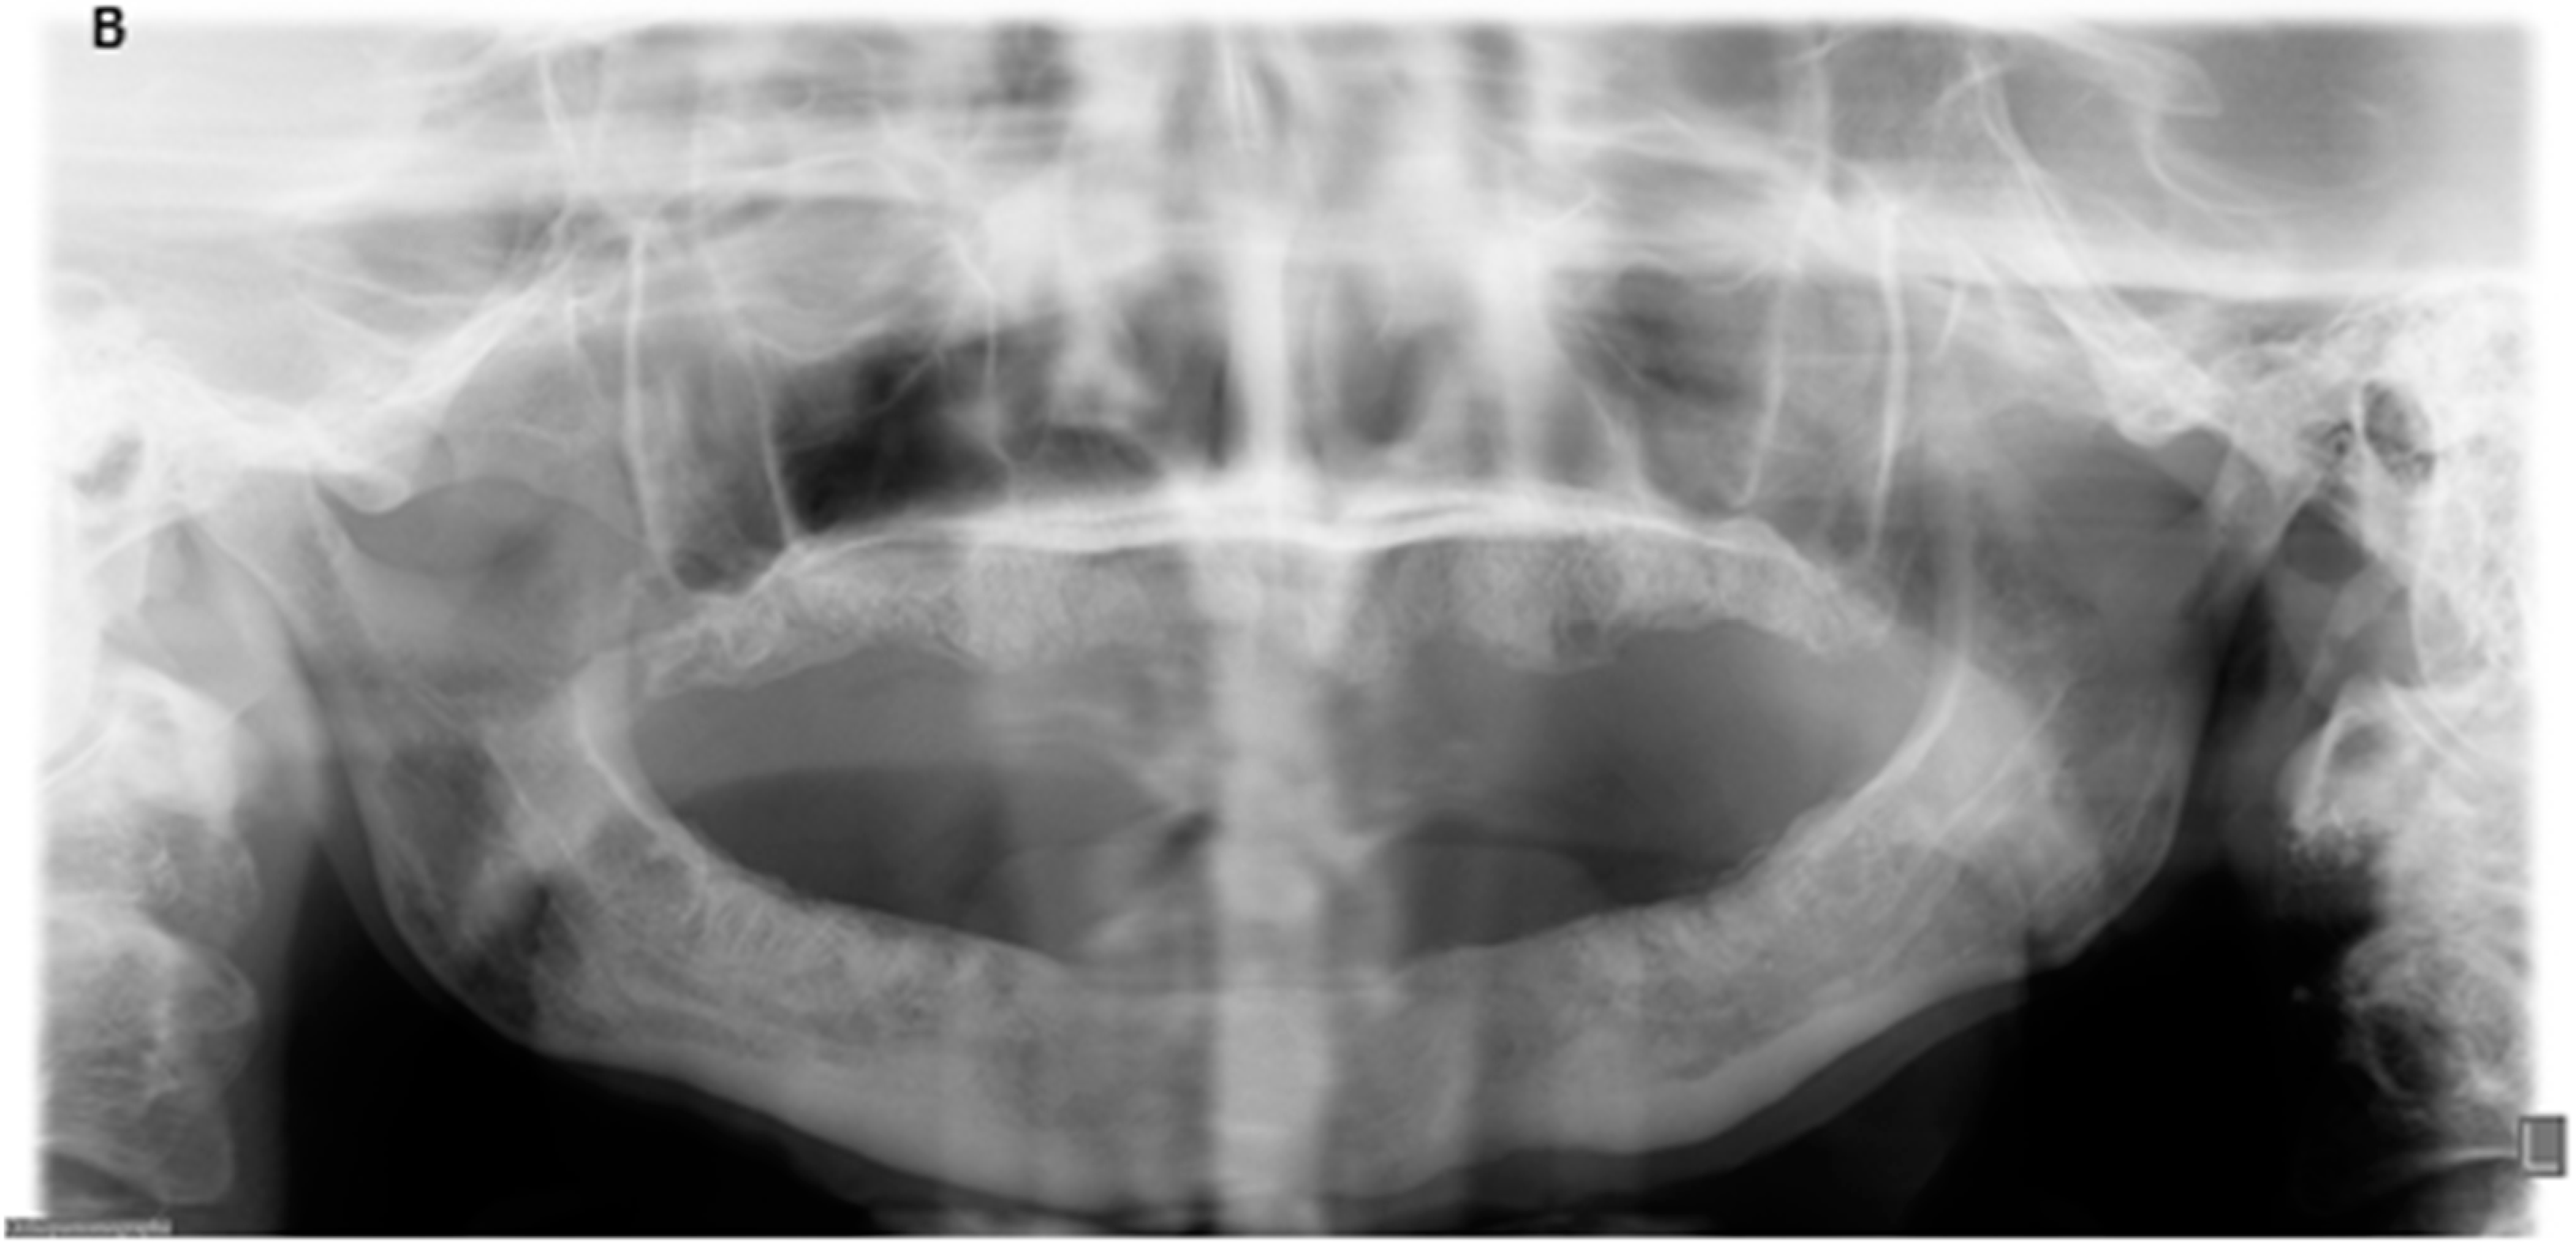

Figure 2.

Radiologic findings before surgery and nine months after surgery. (A) Panoramic radiograph with extensive osteolysis, extending from region 46 to 34 up to the inferior border in the region of the symphyse; (B) Panoramic radiograph nine months post-operatively with healed, smooth edges of the mandibular body.